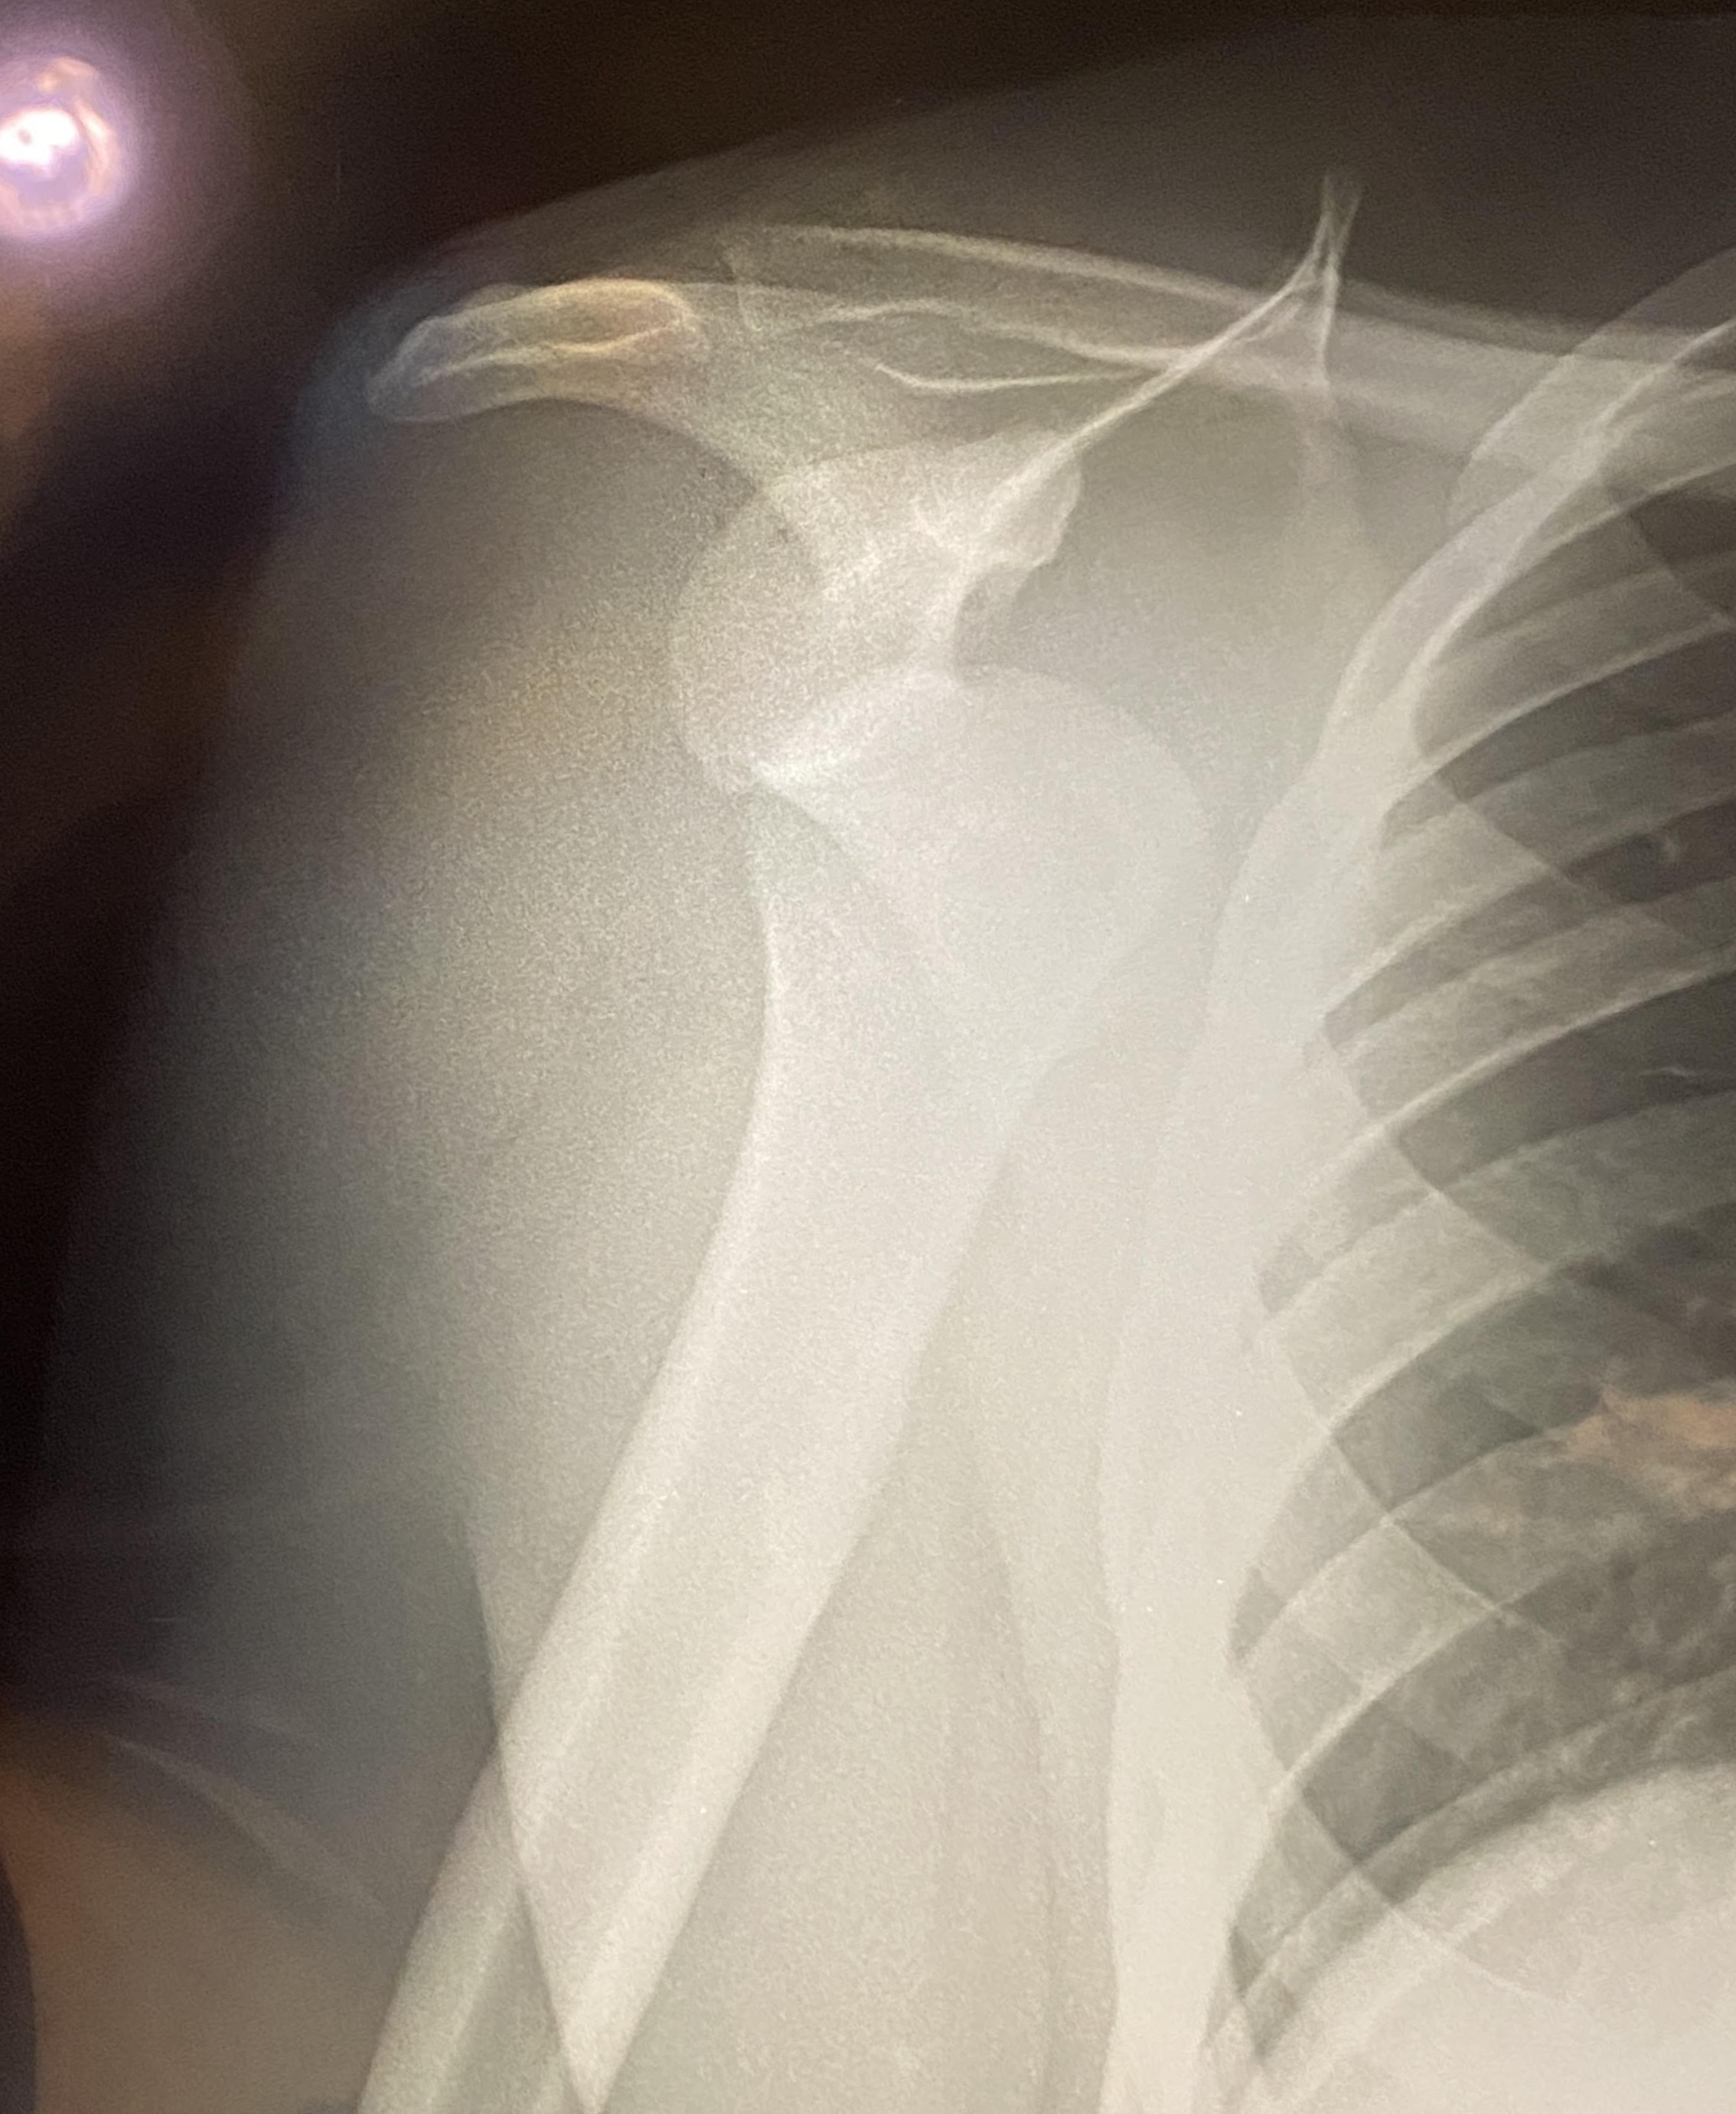

Recently, while surfing at Playa Zicatela in Puerto Escondido, I had a serious accident and dislocated my shoulder. What started as a normal day doing something I love turned into a painful injury that now requires ongoing medical care, physical therapy, and recovery time away from work and everyday life.

Unfortunately, the costs are quickly adding up—ER visit, imaging, consultations, and therapy sessions—and I do not have insurance. That’s why I’m asking for any help you might be able to offer.

Hace poco, mientras surfeaba en Playa Zicatela, Puerto Escondido, sufrí un accidente serio que resultó en una dislocación de hombro. Lo que comenzó como un día normal haciendo lo que más me apasiona, terminó en una lesión dolorosa que ahora requiere atención médica continua, fisioterapia y un proceso de recuperación lejos del trabajo y las actividades diarias.

Lamentablemente, los gastos médicos están aumentando rápidamente—visita al hospital, radiografías, consultas, y terapias—y no tengo seguro. Por eso recurro a ustedes, buscando un poco de ayuda.